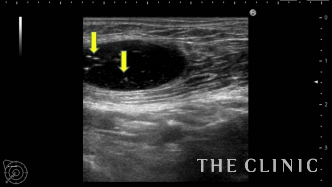

ヒアルロニダーゼが入ると加水分解して白く点状の画像として描出されます。

しこり全体にヒアルロニダーゼが浸透するように十分な量を注入することがポイントです。

ヒアルロニダーゼを注入すると容易にヒアルロン酸を吸引除去することができます。

吸引をしっかり行い、エコー上はすべて消失しました。